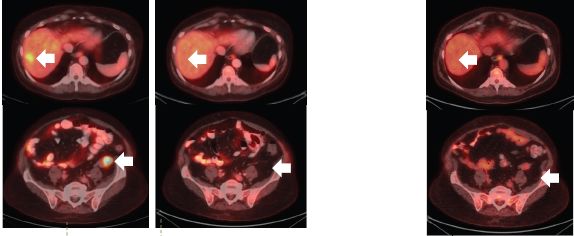

如专为克服拉罗替尼耐药研发的第二代NTRK抑制剂LOXO-195,最初的两位耐药患者尝试新药后,肿瘤再次快速缩小。比如下面这位,用药一个月后,耐药的肿瘤就再次几乎消失!

耐药后 使用2代药一个月后